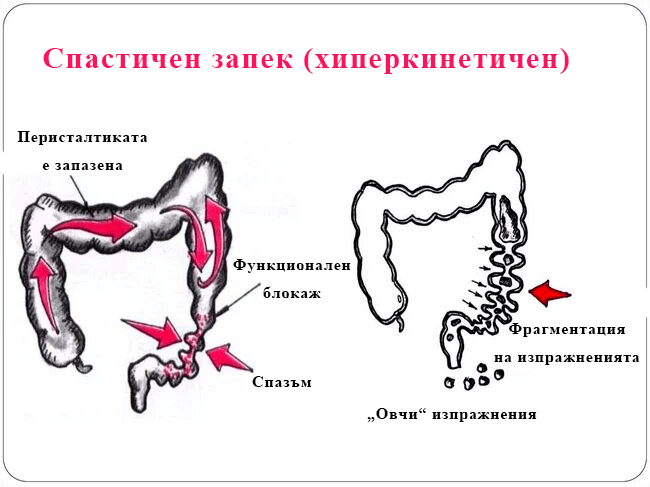

За по-ясна представа, нека първо разберем какво представлява запекът.

Запекът е забавено придвижване на изпражненията през дебелото черво. Обикновено това е свързано с големи количества сухи и твърди изпражнения в изкачващото се дебело черво, които се натрупват заради прекомерното абсорбиране на течности. Всяка патология на червата, която затруднява преминаването на съдържанието (язви, тумори, сраствания, които притискат червото), може да бъде причина за запек.

Запекът е забавено придвижване на изпражненията през дебелото черво. Обикновено това е свързано с големи количества сухи и твърди изпражнения в изкачващото се дебело черво, които се натрупват поради прекомерно абсорбиране на течности. Всяка патология на червата, която затруднява преминаването на съдържанието (язви, тумори, сраствания, които притискат червото), може да бъде причина за запек.

Понякога запекът може да бъде толкова сериозен, че перисталтиката на дебелото черво се случва само веднъж на няколко дни или дори веднъж седмично. Това позволява натрупването на огромни количества изпражнения в дебелото черво, което води до разширяването му до 7,5–10 см в диаметър.